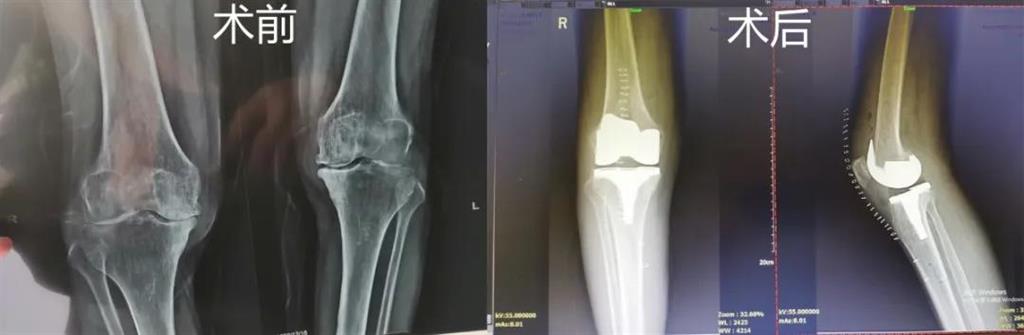

和平國際醫(yī)院副院長、骨科中心主任劉丹在診斷后發(fā)現(xiàn),老人雙側(cè)膝關(guān)節(jié)患有骨性關(guān)節(jié)炎,右側(cè)膝關(guān)節(jié)較為嚴重,而且關(guān)節(jié)磨損嚴重關(guān)節(jié)間隙基本消失。

經(jīng)過進一步檢查后,劉丹帶領(lǐng)團隊在計算機導(dǎo)航系統(tǒng)的輔助下,為老人實施了右側(cè)全膝關(guān)節(jié)置換手術(shù)。術(shù)中出血明顯減少,術(shù)后疼痛腫脹等反應(yīng)輕微,畸形矯正力線恢復(fù)理想,而且功能恢復(fù)快速,術(shù)后四天就可以下地行走。